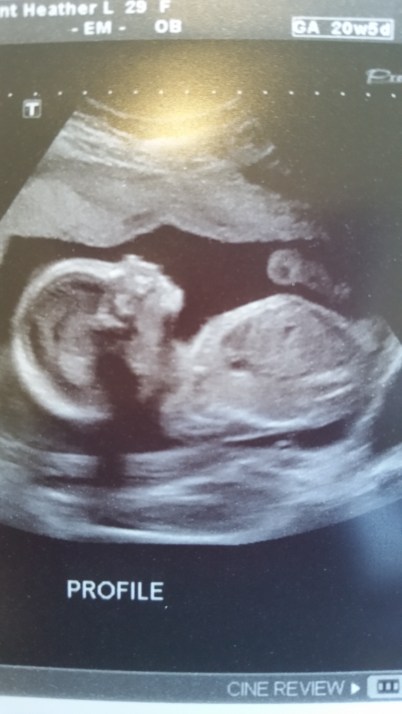

Well, here I am at 21 weeks! I am feeling great and really enjoy being pregnant right now. This week movement has really increased which makes it that much more real. Tuesday we had an ultrasound appointment and midwife appointment afterward. Seeing the baby was so neat! We got to see all different views and angles of the little one. At one point we were watching it face on and could see it’s precious little mouth open and close. The ultrasound tech said that it was most likely swallowing. The tech also showed us it’s heart, spine, brain, kidneys, and bladder. She checked for all the necessary parts…arms, feet, and hands. The baby had it’s middle finger up while checking one of the hands. We had a pretty good laugh! This is the scan that can determine the sex of the baby. If you have been reading for a while, you know that we want the sex of the baby to be a surprise. The technician still checks to make sure everything is developing correctly and had us turn our eyes away from the screen while she took a peak. She tried with no luck because the baby had it’s legs perfectly crossed in front of the goods. Guess we have a very modest baby. She came back to that area a few different times hoping enough time had passed for the baby to move positions. NOPE! That baby was not going to allow her a look. So even if we wanted to find out, the baby wants it to be a surprise. After she printed us some pictures we headed over to see the midwife. Everything is going great and I am measuring exactly where I should be. Later we took a trip to Buy Buy Baby to get a feel for what we want to register for. Walked out of the store feeling a bit overwhelmed. Time to start doing a little research on what to purchase that is both high in quality and value! I’d love to hear any product suggestions you might have in the comments below! A lot has changed in 11 years!

Best Moment this week: Having our ultrasound appointment! Incredible to see how much the baby has grown and makes it that much more real!